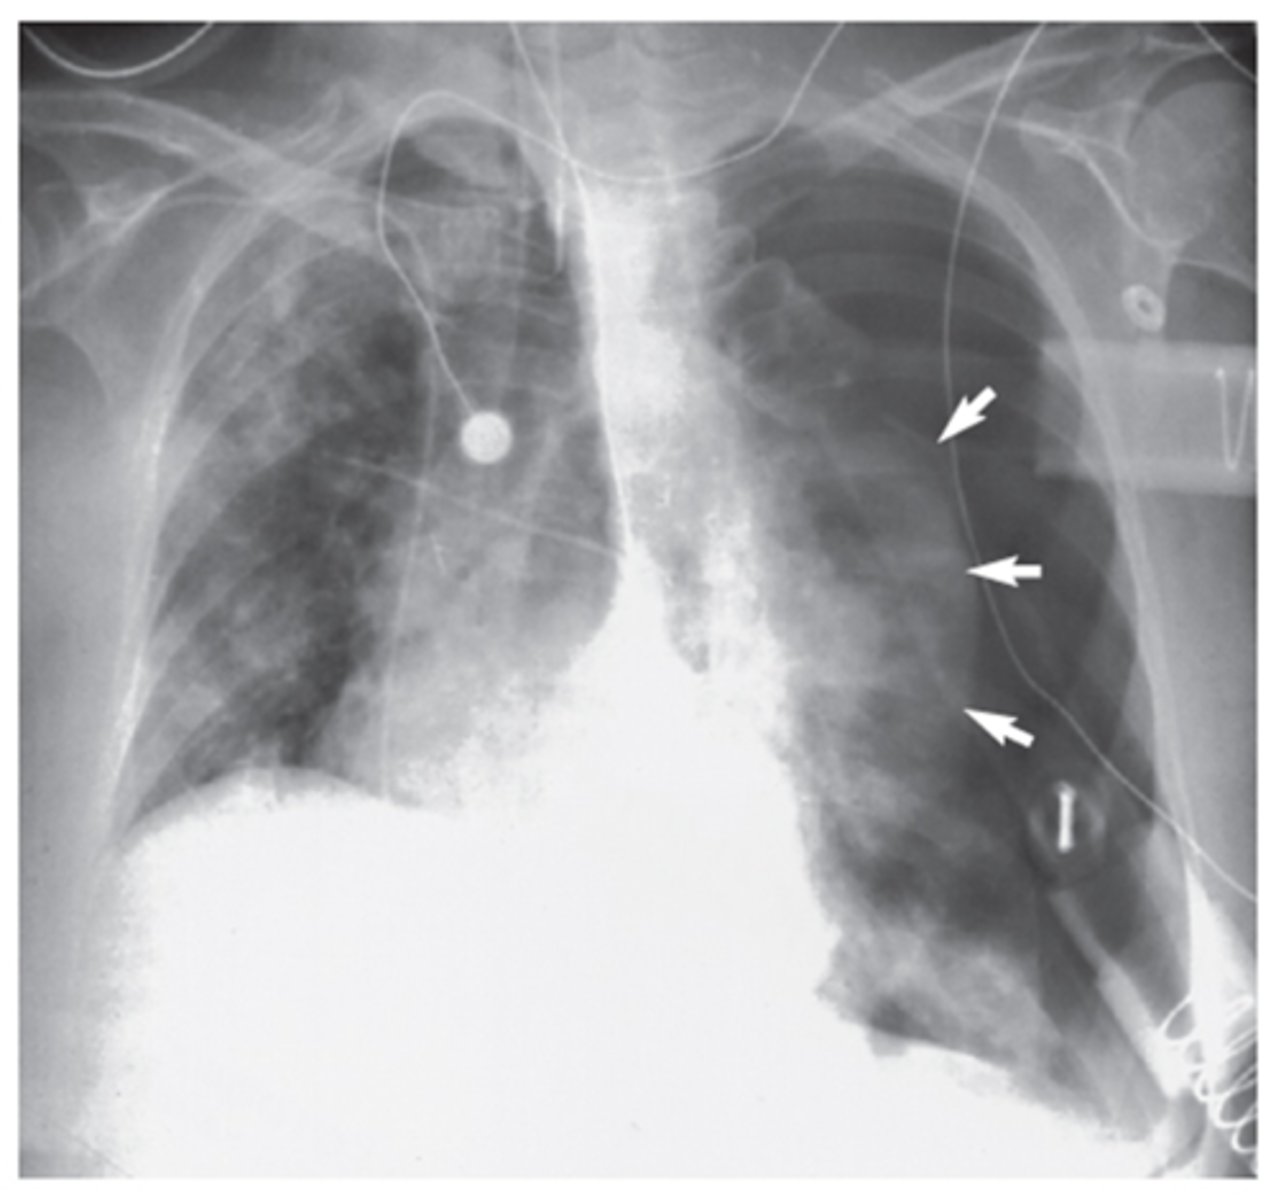

Left lung

Where is the abnormality located in the chest?

Atelectasis

What is the red arrow indicating?

Effusion

What is the likely interpretation?